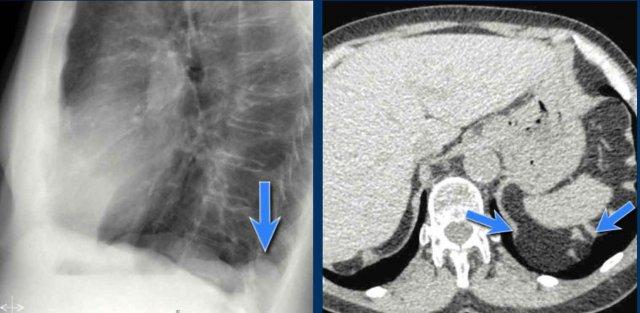

Dịch chuyển đường azygô-thực quản (1) – Thoát vị hoành

Thoát vị hoành (đầu mũi tên) là nguyên nhân phổ biến nhất gây dịch chuyển đường azygô-thực quản quan sát thấy trên phim tư thế thẳng (PA).

Lưu ý hình ảnh khí trong túi thoát vị trên phim tư thế nghiêng (mũi tên đen).

Dịch chuyển đường azygô-thực quản (2) – Hạch to dưới carina

Một nguyên nhân thường gặp gây dịch chuyển đường azygô-thực quản là hạch to dưới carina (trạm 7).

Trên phim X-quang ngực, lưu ý hình ảnh đường azygô-thực quản bị đẩy lên trên ngay dưới carina, phù hợp với hình ảnh hạch bạch huyết dưới carina to (mũi tên đen).

Ngoài ra còn thấy hạch to cạnh khí quản phải, đẩy dải cạnh khí quản phải (mũi tên trắng) và làm lệch khí quản sang trái.